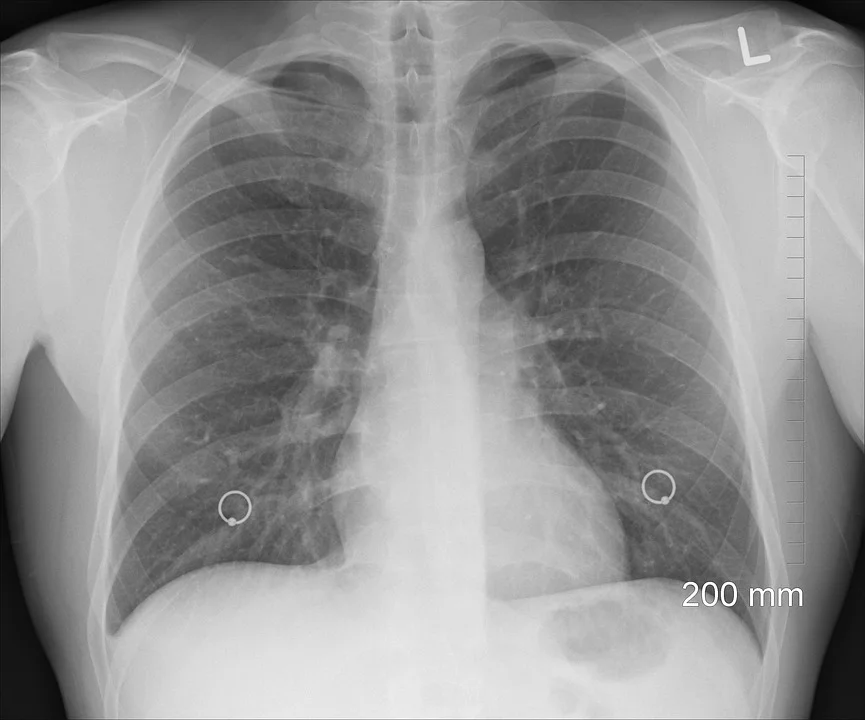

14. Helps Lungs Repair

Melatonin alleviates acute lung injury through inhibiting the NLRP3 inflammasome. R